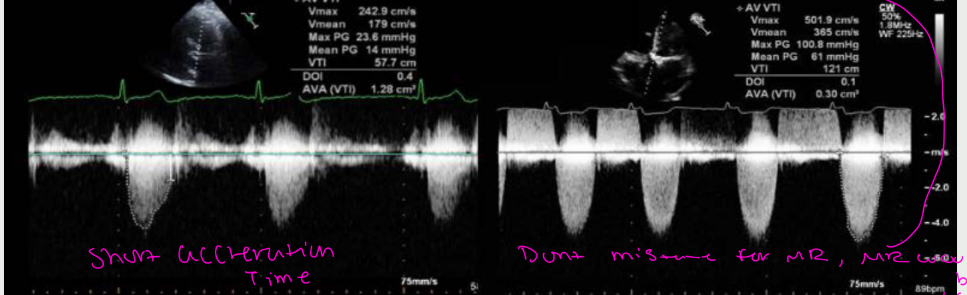

normally the AV demonstrates a what waveform with a what acceleration time. Mild AS left demonstrates a ____ waveform with a what acceleration time. sever AS on the right demonstrates a what waveform with what acceleration time

increased acceleration timeā mean in AS?

š Blood takes longer to speed up because itās pushing through a tight valve.

Why this happens in aortic stenosis

The valve opening is narrow

There is high resistance to flow

Blood cannot accelerate quickly

Peak velocity is delayed

š The tighter the valve ā the longer the acceleration time.

What it looks like on Doppler

Rounded, delayed peak

Slow rise to max velocity

āLate-peakingā waveform

Increased acceleration time in aortic stenosis reflects delayed blood acceleration due to increased resistance across a severely narrowed aortic valve.ā

what is this showing

FIXED DOPPLER

SIGNAL VERSES

DYNAMIC

DOPPLER SIGNAL